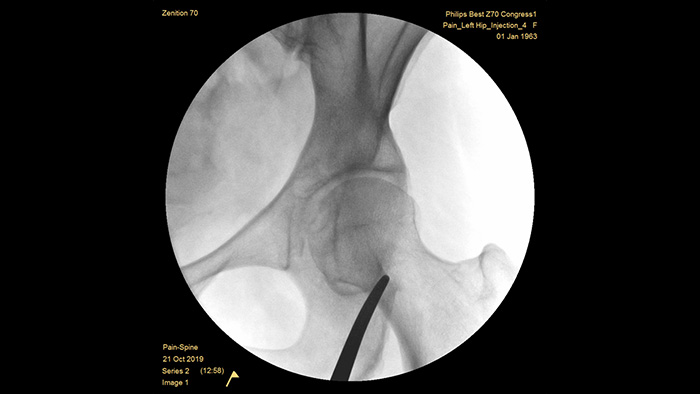

Philips se ha forjado una reputación de excelencia en la obtención de imágenes y la eficiencia de las dosis a lo largo de medio siglo de experiencia en el desarrollo de sistemas de arco en C móviles para el entorno quirúrgico. Nuestras soluciones de cirugía móvil Zenition se basan en un enfoque integral de la gestión de dosis. Proporcionan una calidad de imagen clínicamente relevante durante los procedimientos intervencionistas para aplicaciones de gestión del dolor, al tiempo que gestionan, de forma eficiente, la exposición a la radiación de los pacientes y el personal médico.

Mejora automática de la imagen

MetalSmart excluye automáticamente los artefactos metálicos causados por los implantes metálicos para proporcionar una mayor calidad de imagen y un control eficiente de la dosis para los procedimientos de tratamiento del dolor y para los pacientes con implantes metálicos, en comparación con los sistemas sin exclusión de metales. BodySmart favorece la obtención de imágenes correctas a la primera y la eficiencia de la dosis ya que adapta, de forma automática, el campo de medición a la zona de interés.

Profundidad óptima del arco C

La profundidad óptima del arco en C totalmente contrabalanceado proporciona un amplio espacio para posicionarse alrededor de los pacientes obesos, y obtener imágenes de la columna lumbar y la cadera. Admite la colocación sobre la mesa, incluso para las mesas que tienen una base grande.